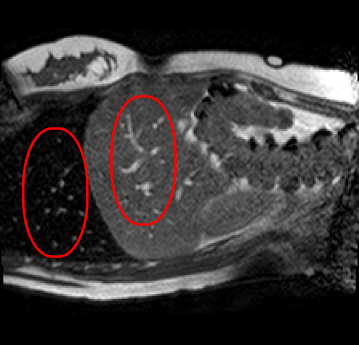

With this motivation, [6] proposed a convolutional neural network (CNN) based approach for temporal interpolation of navigators. Their CNN takes as inputs a fixed number of acquired images and learns to predict the missing images directly in the intensity space. This approach, which we call the Simple Convolutional Interpolation Network (SCIN), is a ’black-box’ formulation that does not incorporate any prior information about the interpolation process. Image prediction is guided only by the cost function used to optimize the network parameters. The issue with this is that it is unclear whether the image similarity measures that are generally used as cost functions suffice to ensure fidelity of the generated images to the original images. Indeed, Fig. 1b shows a case where an image interpolated using SCIN is quite blurry and misses several liver and lung structures present in the original image.

(a) (b) (c)

Qualitative results are shown in Fig. 4. We observe no large qualitative differences in the performances of MFIN and MFINc for either loss function. Since, MFINc-SSIM provides the best quantitative results, we show interpolated images from this method and compare them against SCIN-SSIM. Both methods perform well when the motion between the neighbouring images is low. This is reflected in the absence of any structures in the error images in Fig. 4.1. However, RMSE is lower for SCIN because it produces a denoised interpolated image, while MFIN carries over the noise pattern from the neighbouring known image. Whenever there exists high motion between the images being interpolated, SCIN produces blurry images and often misses image structures. This can be observed in cases 2-4 in Fig. 4. For all these cases, MFINc (and also MFIN) produces sharp images and largely preserves structures in the images. Fig. 4.2 shows a case where MFINc additionally has a much better performance with respect to image alignment. Fig. 4.3 shows a representative case, with small improvement in image alignment, yet worse RMSE and SSIM values for MFINc. Finally, Fig. 4.4 shows a case, where MFINc produces worse alignment of structures than SCIN.